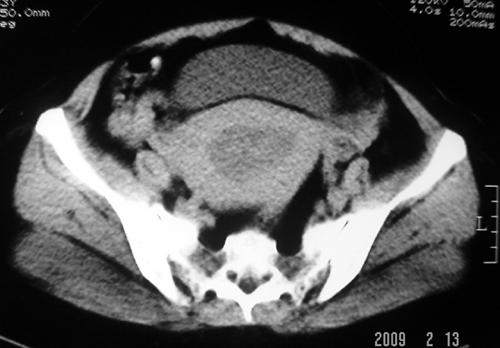

以下是引用余辉在2009-2-14 8:37:00的发言:[br]宫颈左后壁见较大低密度肿物影且向左后上方突出,宫腔内见大片状低密度区,考虑宫颈肿瘤,宫颈癌可能性大,伴宫腔积液或转移